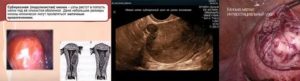

Виды миомы и их влияние на общее состояние женщины

- Субсерозные узлы отличаются тем, что растут они наружу. Обячно такая миома протекает безсимптомно. Однако если образованный узел крепится к матке тонкой ножкой, это может стать проблемой так как при перекручивании ножки возможны сильные боли, вплоть до обморока. При интенсивном росте такой миомы может возникнуть кровотечение и давление на прилегающие органы.

- Субмукозные узлы располагаются под слизистой оболочкой матки и растут внутрь — в полость. Эта форма чаще всего сопровождается маточными кровотечениями, нарушениями цикла и болями в нижней части живота. Характерен для этого вида миомы быстрый рост узлов.

- Интерстициальные узлы – располагаются между связками. При множественных интерстициальных миомах возможны обильные кровотечения во время менструации.

- Интрамуральные узлы растут в мышечном слое миометрия.